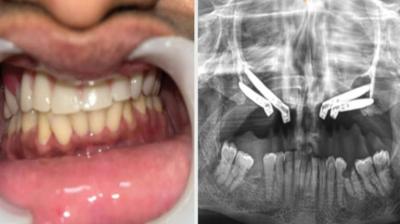

24 वर्षीय युवती के चेहरे पर लौटी मुस्कान और आत्मविश्वास

6 Sep, 2025 10:00 PM IST | SHABDSARANSH.COM

एम्म में जटिल सर्जरी को सफलतापूर्वक अंजाम दिया है। इस सर्जरी में ट्यूमर के कारण काटे गए निचले जबड़े को पैर की हड्डी से दोबारा बनाया गया और उसमें 13...